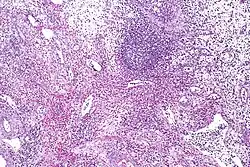

Eosinophilic cystitis showing edematous and chronically inflamed lamina propria with numerous eosinophils.

Cystoscopy typically reveals large mucosal edema along with erythematous, polypoid, velvety red lesions. It can be mistaken for vesical rhabdomyosarcoma in children.[25] Eosinophilic cystitis is hard to differentiate from other cystitis types (like interstitial and tuberculous cystitis), neoplastic lesions (like carcinoma in situ), and other bladder cancers. Therefore, in order to confirm the diagnosis of eosinophilic cystitis, biopsies are required.[2] Transmural inflammation is present histologically, primarily with eosinophils. The lamina propria has more severe edema and inflammation. A contracted bladder may result from focal muscle necrosis and varying degrees of detrusor muscle fibrosis.[26]